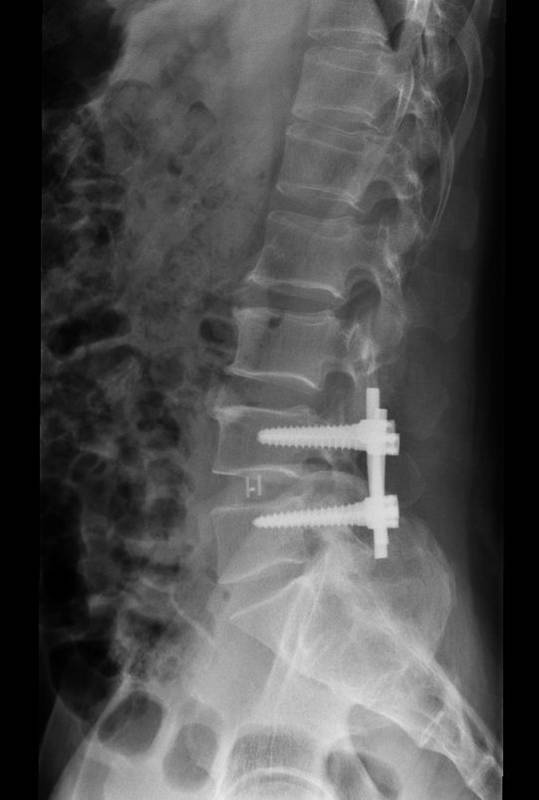

诊断:腰椎间盘脱出症,髓核游离 入院后完善检查,查无手术禁忌症后行腰椎间盘切除椎板减压椎弓根钉椎间融合器植骨内固定术

患者早期手术治疗后,支具保护下可以早期下地,患者腿部疼痛减轻,提高患者生命质量。